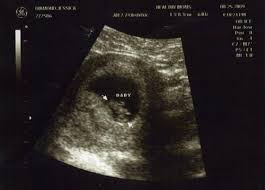

Week 4 or 5. A missed period is usually the first noticeable sign of pregnancy. At 3 weeks pregnant your baby does not yet exist but this is actually the week implantation happens. You might have heard of something called implantation bleeding which occurs anywhere from six days to two weeks after conception.

Timeline from missed period mild cramping and spotting. It occurs anywhere from six to 12 days after the egg is fertilized. About 5 to 6 days after ovulation the fertilised egg burrows into the lining of the womb this is called implantation. This mass of cells is called blastocytes.